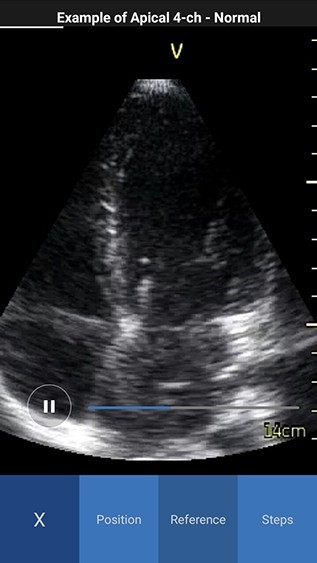

Scan Coach reference window displays with three tabs - Reference, Position and Steps.

- Reference - Provides access to multiple ultrasound image examples for normal view and a few common pathologies for the current scan plane. You can access all available reference images swiping left or right.

NOTE: By default the reference image tab is activated when you press the info icon for the first time. The white color in the image header represents an example of a normal image, while red color represents an example of a pathology image.

Reference Image Normal